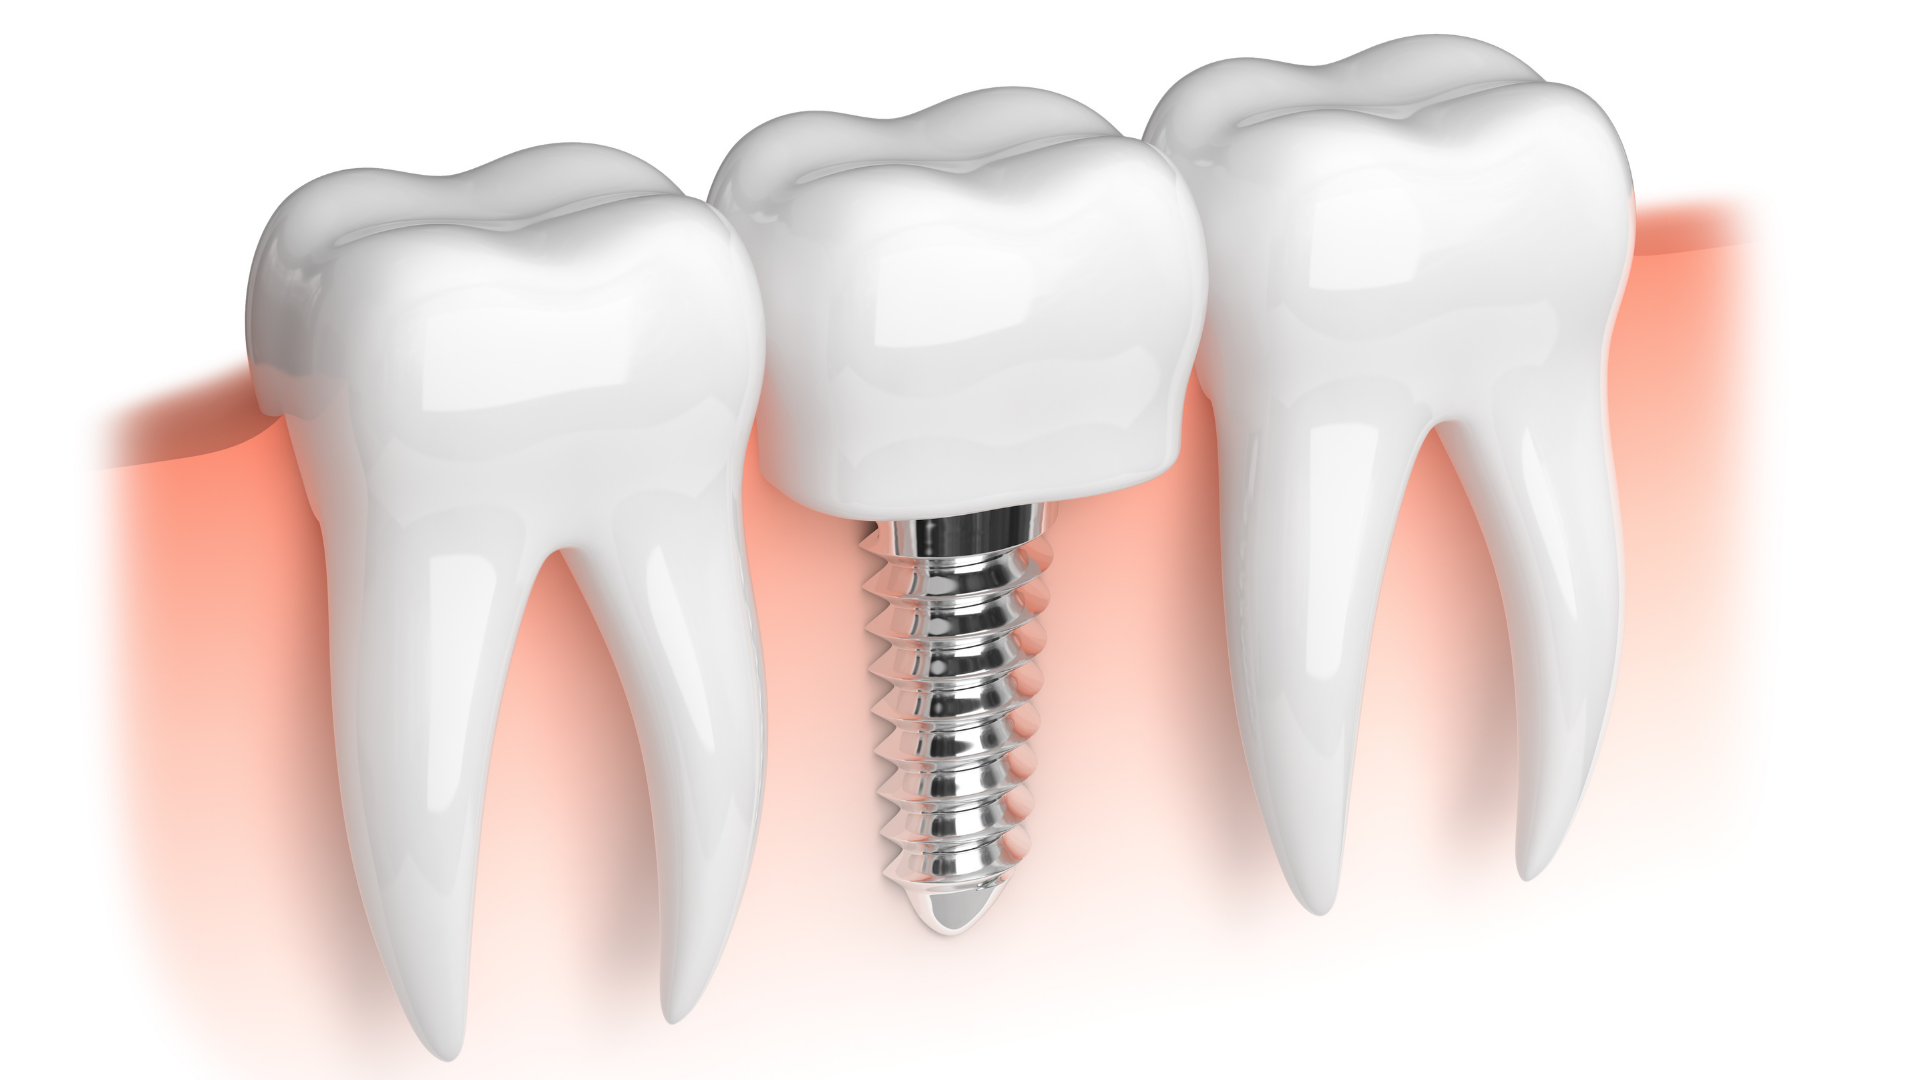

O implante dentário funciona como uma raiz artificial, geralmente feita de titânio, que é fixada no osso para substituir o dente ausente.

Após o período de integração óssea, uma coroa personalizada é instalada, reproduzindo fielmente o formato, a cor e o brilho dos dentes naturais.

Existem diferentes tipos de implantes dentários, e a escolha depende do caso clínico e do objetivo do tratamento:

Implante unitário: substitui um único dente perdido.

Implante múltiplo: indicado para reabilitar várias ausências dentárias.

Protocolo sobre implantes: usado em pacientes que perderam todos os dentes de uma arcada, fixando uma prótese completa com estabilidade e conforto.

Implante zigomático: opção para casos com grande perda óssea, onde os pinos são fixados no osso zigomático (maçã do rosto).